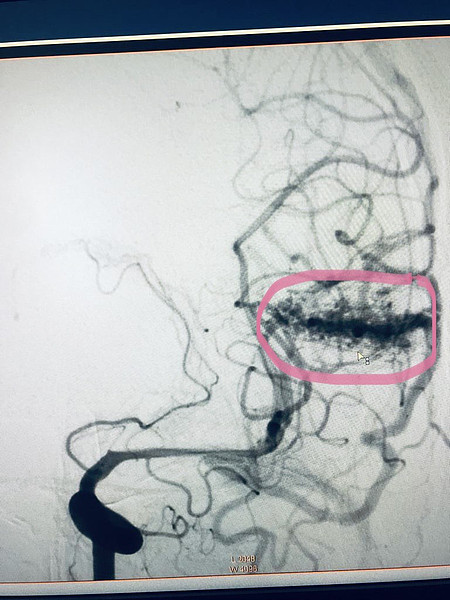

авм.